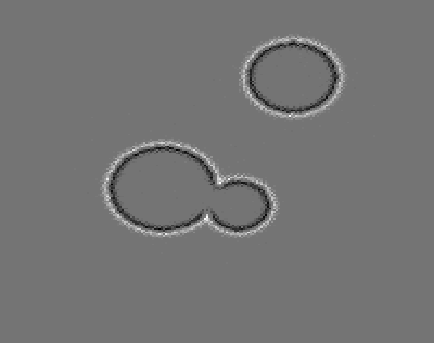

4.1 Reconstruction of the Laplacian feature map

We first investigate the feasibility of the proposed approach for recovering the Laplacian of the initial image. For our first experiment, we use a phantom image, which is defined as a characteristic function of the union of three discs and has the size N×N𝑁𝑁N\times N with N=200𝑁200N=200, cf. Figure 1(a). Since, according to the sampling condition (2.5), full aliasing free angular sampling requires πNs=472𝜋subscript𝑁𝑠472\lceil\pi N_{s}\rceil=472 samples in the s𝑠s-variable, we computed tomographic data at 2Ns+1=3012subscript𝑁𝑠13012N_{s}+1=301 equally spaced signed distances s[1.5,1.5]subscript𝑠1.51.5s_{\ell}\in[-1.5,1.5] and at Nφ=40subscript𝑁𝜑40N_{\varphi}=40 equally spaced directions in [0,π)0𝜋[0,\pi). This data is properly sampled in the s𝑠s-variable, but undersampled in the angular variable φ𝜑\varphi, cf. Figure 1(b).

From this data, we computed the approximate Laplacian reconstruction, shown in Figure 1(c), using the standard FBP algorithm in combination with the LoG-filtered data uLoGsyΘsubscript𝑠subscript𝑢LoGsubscript𝑦Θu_{\rm LoG}\circledast_{s}y_{\Theta} that we computed in a preprocessing step using the LoG data filter from Proposition 3.4. It can be clearly observed that FBP introduces prominent undersampling artefacts (streaks), so that many edges in the calculated feature map are not related to the actual image features. This shows, that the edge maps computed by FBP (from undersampled data) can include unreliable information and even falsify the true edge information (since artefacts and actual edges superimpose). In a more realistic setup, this could be even worse, since artefacts may not be that clearly distinguishable from actual edges.

Refer to caption

(a) Phantom

(b) CT data

(c) FBP-LoG reconstruction

Figure 4.1: Reconstruction of the Laplacian feature map using FBP. The phantom image of size 200×200200200200\times 200 consisting of a union of three discs (1(a)) and the corresponding angularly undersampled CT data, measured at 40 equispaced angles in [0,π)0𝜋[0,\pi) and properly sampled in the s𝑠s-variable with 301301301 equispaced samples s[1.5,1.5]subscript𝑠1.51.5s_{\ell}\in[-1.5,1.5] (1(b)). Subfigure (1(c)) shows the Laplacian of Gaussian (LoG) reconstruction using the standard FBP algorithm. It can be clearly observed that FBP introduces prominent streaking artefacts that are due to the angular undersampling.